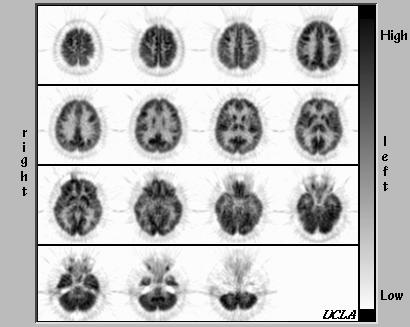

- At Risk for Huntington's Disease; Clinically and Metabolically Normal

Although this particular patient is at risk for Huntington's disease, the FDG-PET scan is metabolically normal. Note that in this case, the diagnosis was not drawn from the PET scan!